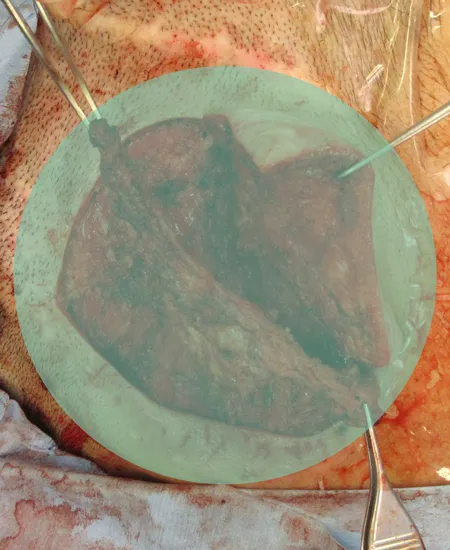

STEP 02

耳介再挙上術のデザインです。

耳は高さの無い状態です。